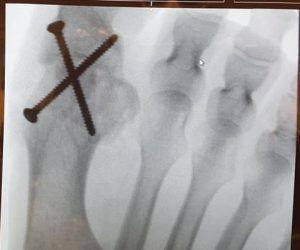

Jag väntar fortfarande på att det ska börja göra ont efter operationen. Det var ju ändå ett hyggligt ingrepp. De första timmarna tänkte jag att lokalbedövningen inte släppt ännu. Men nu, ett dygn senare, har den förstås släppt. Och jag har inte särskilt ont. Jag tar förvisso smärtstillande och är mestadels liggandes med foten i högläge. Men jag hade trott det skulle göra infernaliskt ont ett par dagar. Icke så. Känns ungefär som stortån värkte efter målgången på Hässelbyloppet för tre dagar sedan. Men visst, vad är väl en spik i foten, eller två?